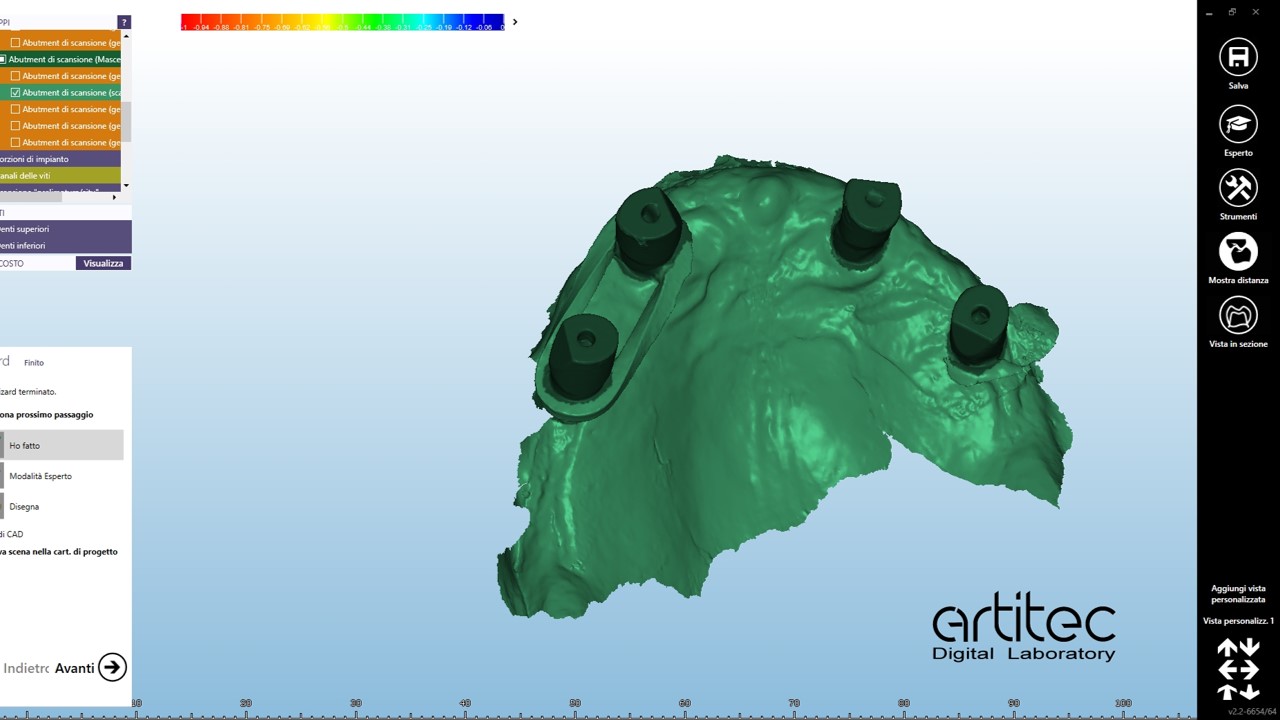

foto 09 scan body superiore

foto 10 scan body superiore allineati- best fit

foto 11 scan body inferiore

foto 12 scan body inferiore allineati

La fase protesica inizia con la ribasatura delle protesi provvisorie per rilevare la corretta anatomia della cresta. Quindi si procede a scansionare con scansione intraorale le impronte ottenute fuori dal cavo orale, poi le protesi provvisorie ribasate ricollocate nel cavo orale e la loro occlusione. Infine, si scansionano le creste edentule dopo aver posizionato gli scan body per tecnica digitale per rilevare la posizione degli impianti. Per la pianificazione sono scattate delle fotografie intraorali ed extraorali per la definizione dei limiti perimetrali del volto al fine di poter eseguire la programmazione del caso tramite il software di previsualizzazione. Le scansioni così ottenute sono poi inviate al laboratorio per la realizzazione di un prototipo delle protesi in prova.